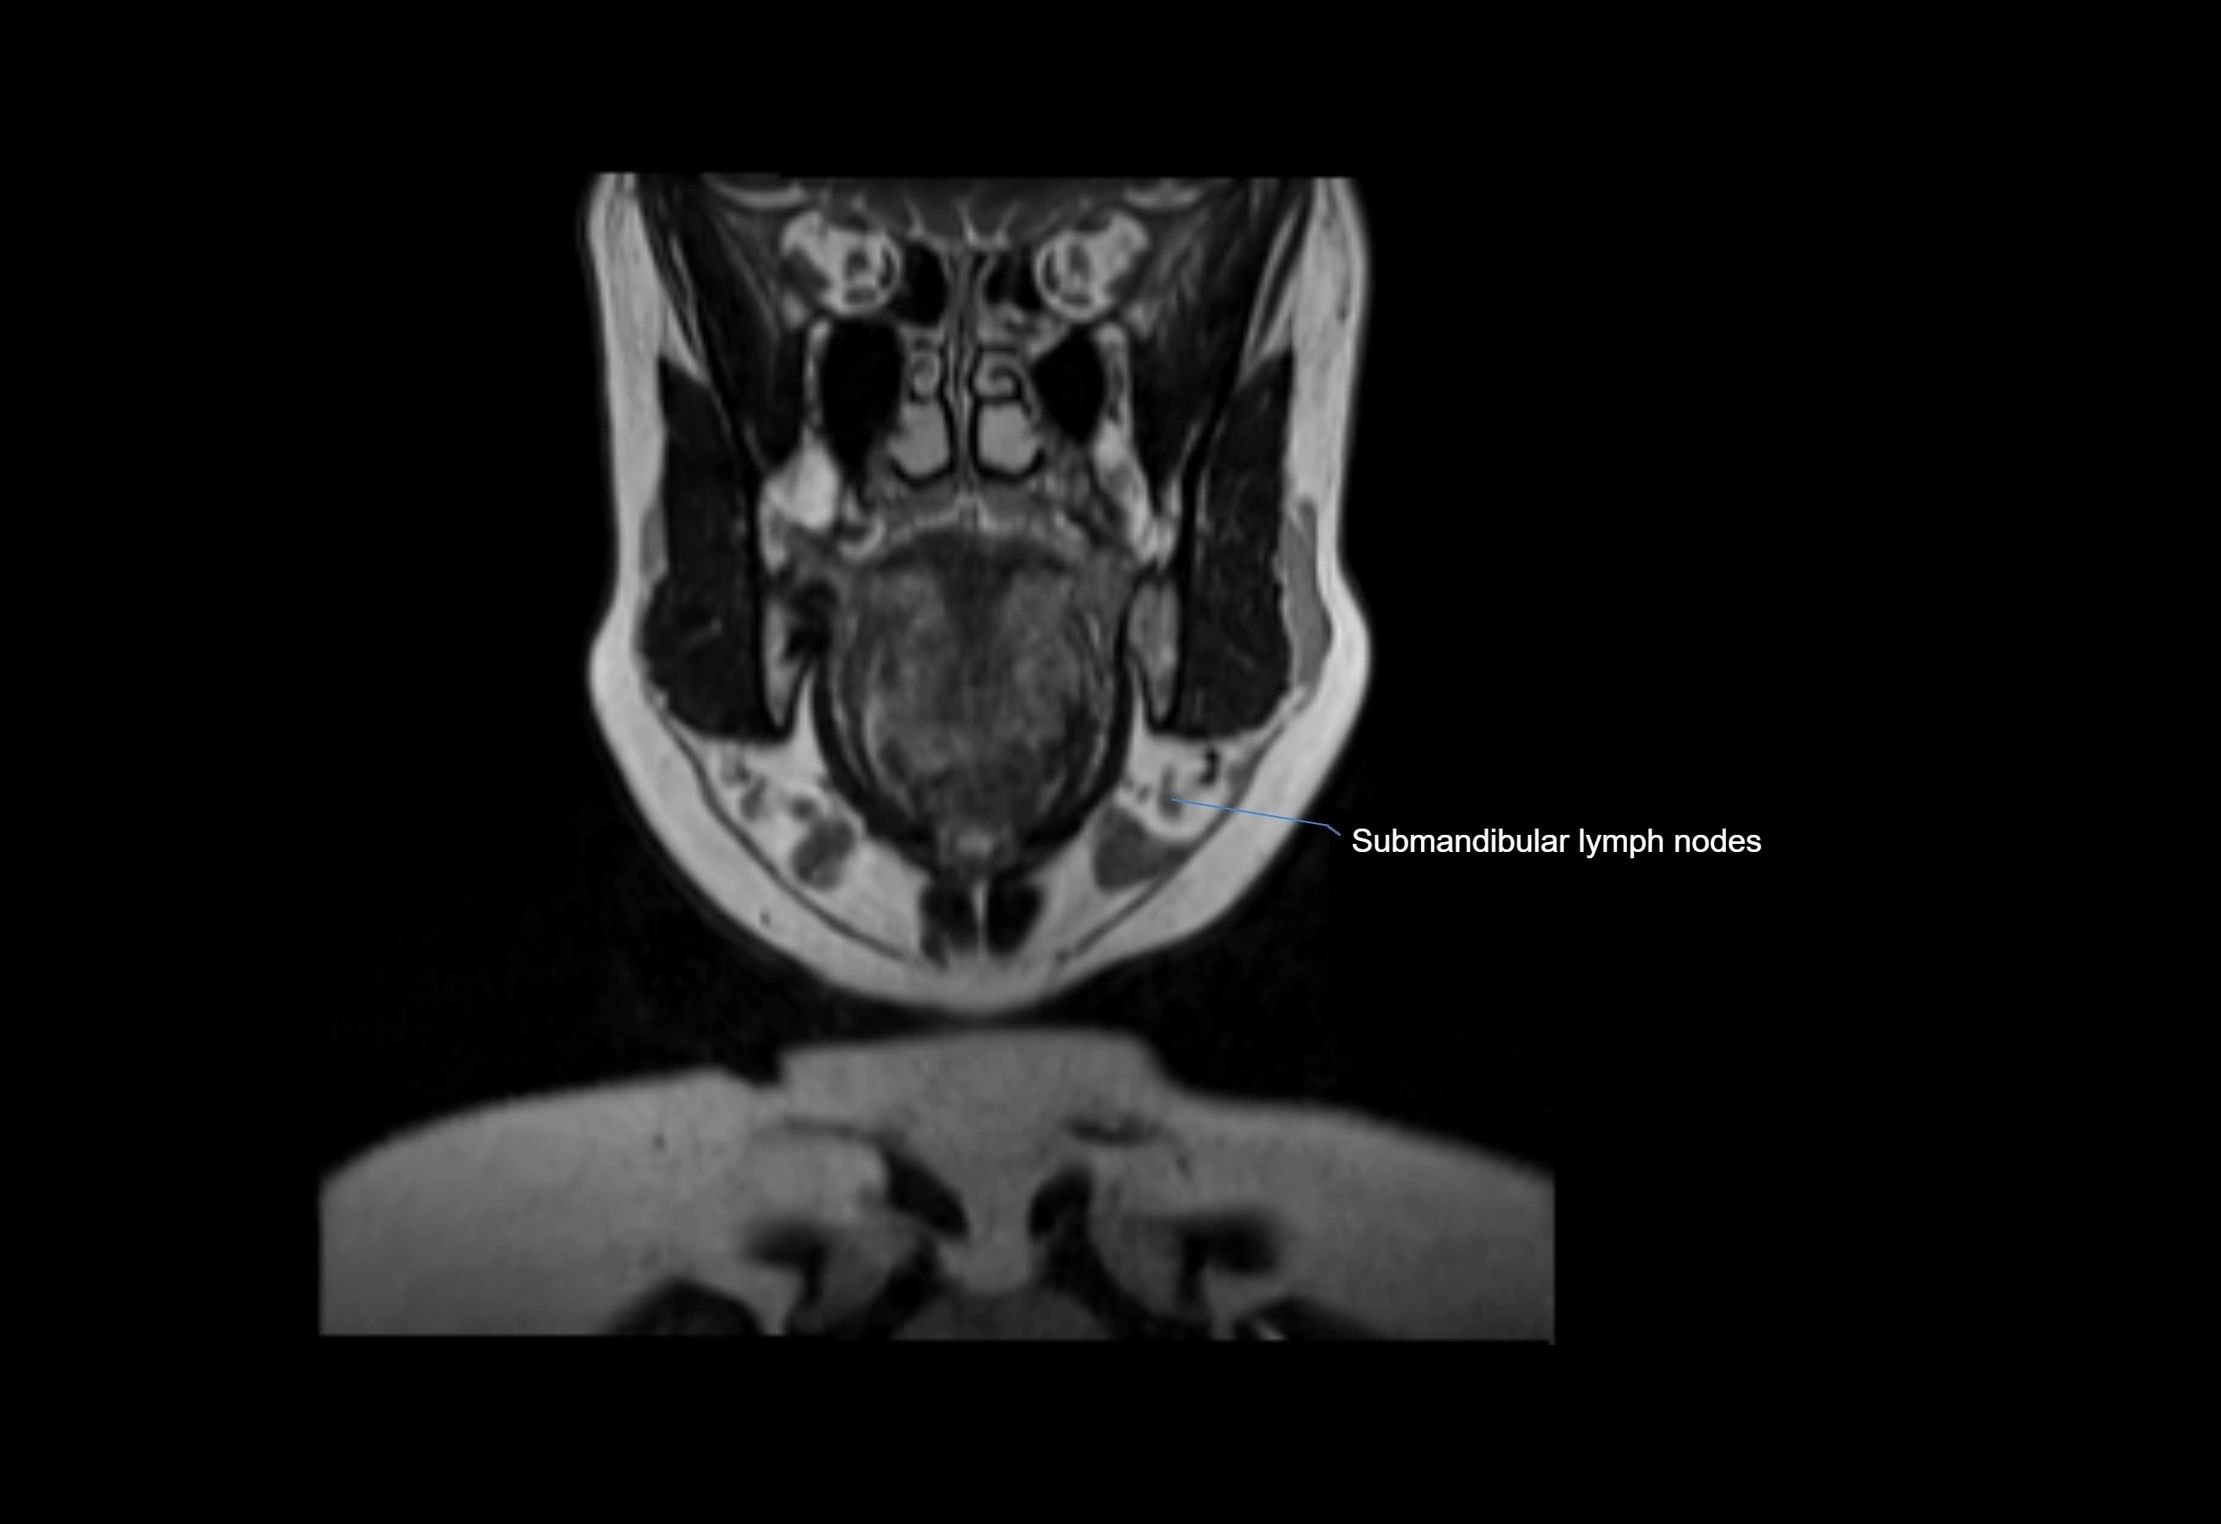

MRI Appearance

T1-weighted images:

• Normal accessory nodes appear as small, oval hypointense to intermediate signal structures within subcutaneous fat

• Surrounded by hyperintense fat, enhancing contrast for visualization

T2-weighted images:

• Nodes show intermediate signal, with surrounding fat bright

• Useful for detecting edema, inflammation, or infiltration

• Fatty hilum may appear slightly hyperintense relative to cortex

MRI images

image